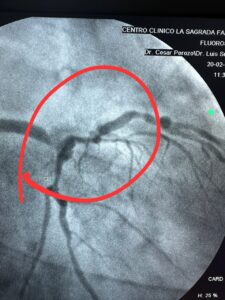

Álvaro Yépez, de 67 años, enfrenta una situación crítica de salud, tras ser diagnosticado con síndrome coronario crónico (SCC), con una lesión ateromatosa oclusiva crítica del 99 % en el tercio distal del tronco de la coronaria izquierda.

Por esta razón requiere una cirugía de corazón abierto lo antes posible, ya que su vida corre un riesgo inminente si la arteria se cierra completamente.